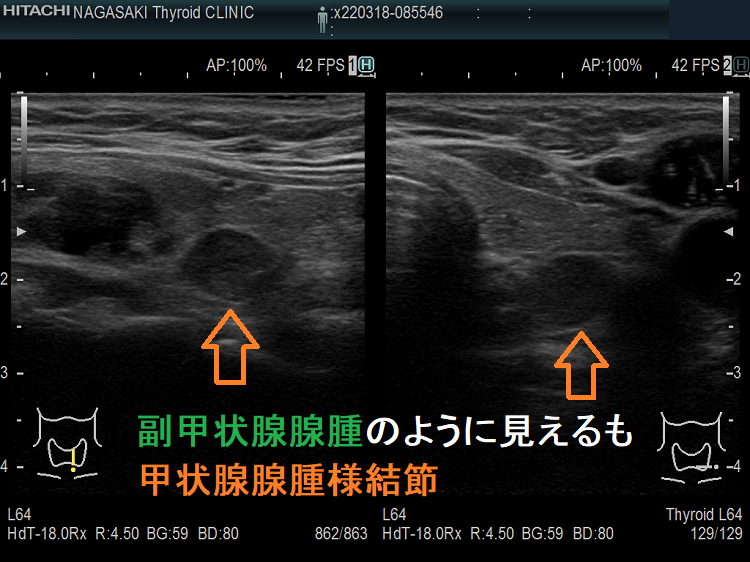

副甲状腺腺腫のように見えるも、実は排液後の甲状腺腺腫様結節

副甲状腺腺腫と同じような位置(写真では左甲状腺の背側)にあり、甲状腺の中なのか外なのかはっきりしません。副甲状腺腺腫のように見えるも、実は甲状腺の中にある甲状腺腺腫様結節。その他、排液後の甲状腺腺腫様結節も副甲状腺腺腫と同じように見える場合もあります。